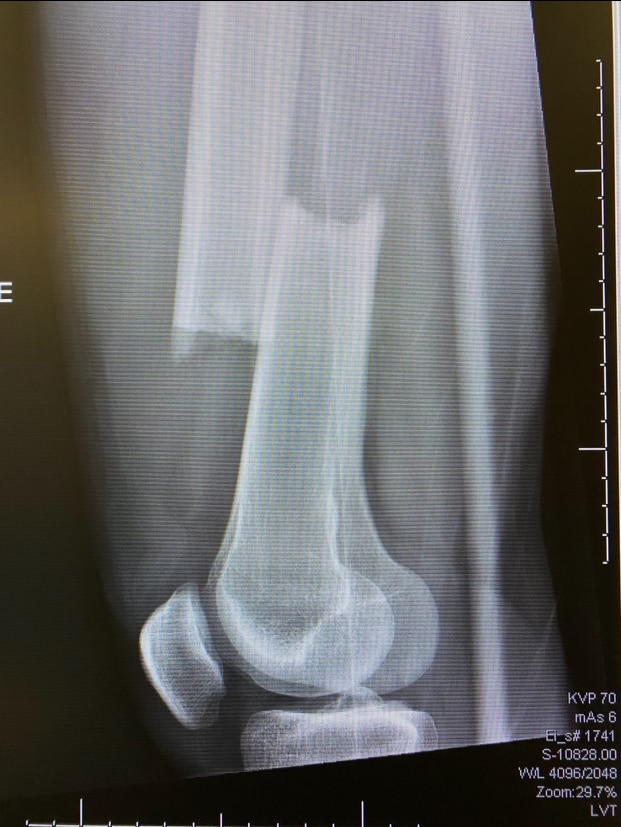

With a minute gone in the second period, Brodzinski skated the puck across the middle of the offensive zone. Eagles forward Trevor Kuntar hustled towards him from the opposite direction. The collision left Brodzinski on the ice, grabbing for his right leg. His femur was completely broken, a clean break.

Two hours later, he was in surgery at a local hospital getting a metal rod put in his leg.

Easton Brodzinski's broken right femur. Easton Brodzinski's right femur was described as a clean break.